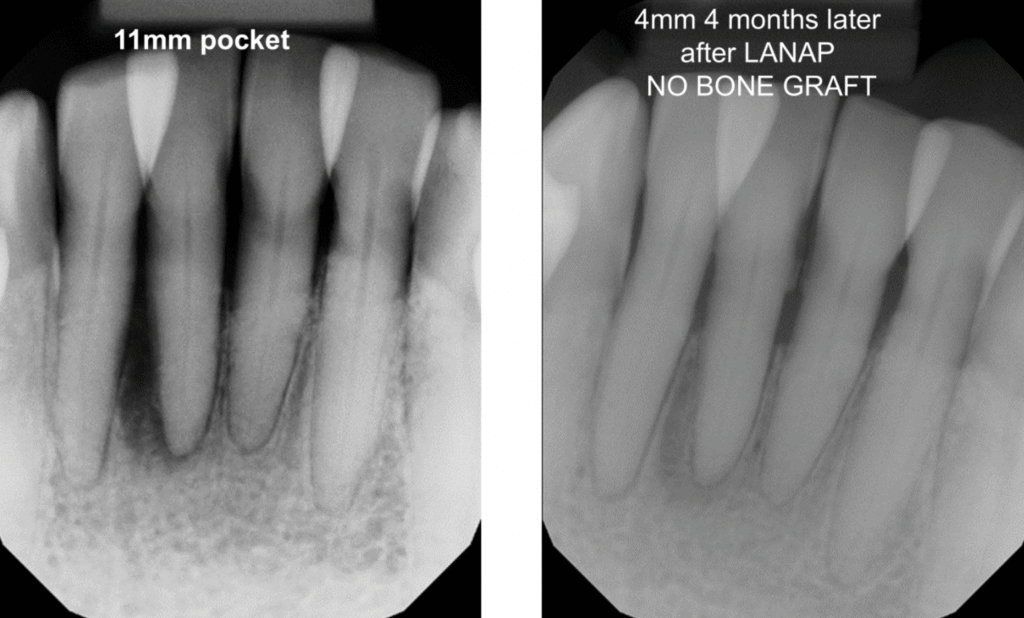

Laser treatment is effective at removing diseased tissue, reducing harmful bacteria, and stabilizing gum disease when used in appropriate cases. It is designed to treat infection while preserving healthy gum and bone structure.

Laser treatment differs from traditional gum surgery in several important ways. It does not involve surgical incisions or sutures and selectively targets infected tissue. This results in less tissue disruption, reduced bleeding, and a shorter recovery period compared to flap surgery.